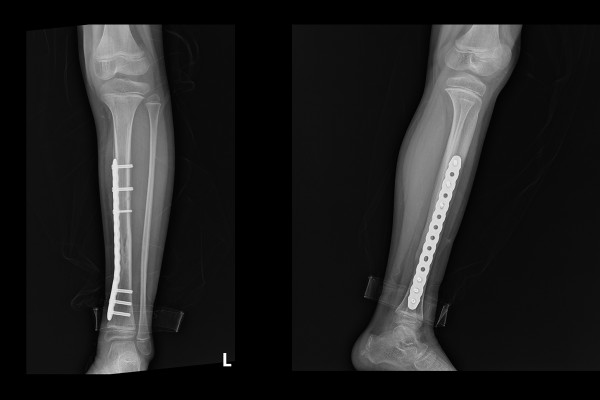

환자분과 보호자분께 현재 뼈 상태와 수술적 치료의 필요성을 설명드렸고, 소아 정강이뼈 골절정복술 및 내고정술(ORIF c MIPO plate for Fx. distal dibia shaft lowerleg Lt.)을 시행하였습니다.

실시간 X-RAY인 C-ARM을 이용해 확인하면서 어긋나있던 골절선을 맞추어 올바른 정렬을 이루게 한 뒤, 금속판(Plate)으로 강하게 고정해줍니다.

수술 후 X-RAY를 보면 강하게 고정되어 어긋남 없이 올바르게 정렬된 것이 확인됩니다.